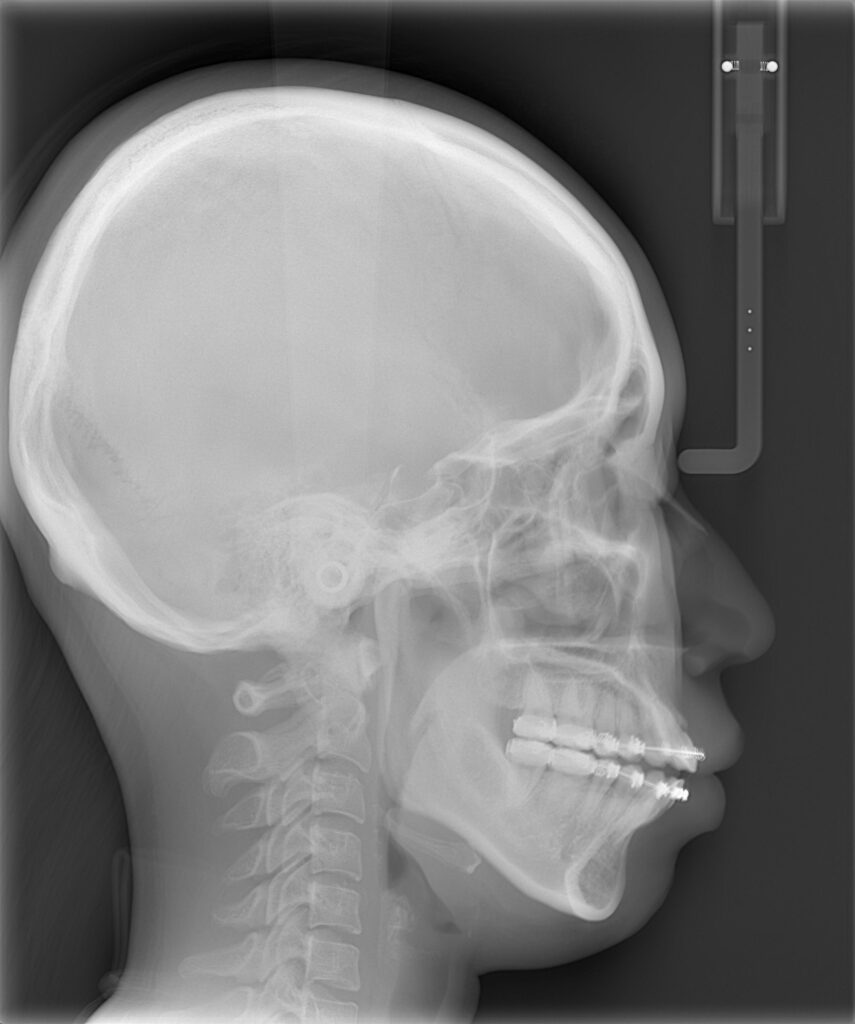

手術は、上あごの位置を整える「ルフォーⅠ型骨切り術」、下あごの位置を調整する「下顎枝矢状分割術」、そしてあご先を前に出す「オトガイ形成術(前進術)」を同時に行いました。

上あごは全体を後方へ3mm移動し、さらにわずかに回転を加えることで、開咬がしっかり閉じるよう調整しています。

あご先(オトガイ)は10mm前方へ移動させ、横顔のバランスを整えました。